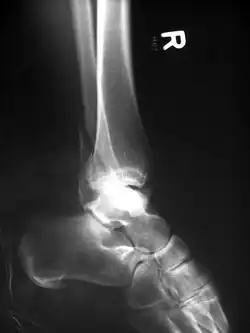

Eine Bimalleolarfraktur im seitlichen Röntgenbild … -

… und von vorne … -

… mit Zuggurtung am Innenknöchel und Platte am Außenknöchel versorgt